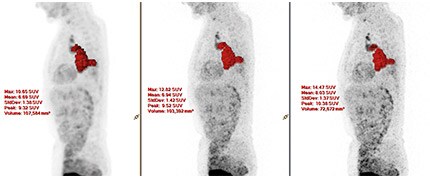

Технологии ×Fine and ×Sharp повышают качество изображений благодаря улучшенному разрешению. Реконструкция с использованием технологии ×Fine (в центре) и реконструкция при помощи ×Fine и ×Sharp (справа).

При тестовом исследовании всего тела пациента, выполоненного специалистами больницы Зальцбургского универститета (Австрия), технология ×Sharp помогла улучшить визуализацию малых поражений. Применение ×Sharp позволило получить более высокие значения SUVmax по сравнению с результатами сканирования, проводившегося без этой технологии. Размер поражений при этом находился в диапазоне 12–20 мм.

Изображения предоставлены клинической больницей Зальцбургского университета, Австрия